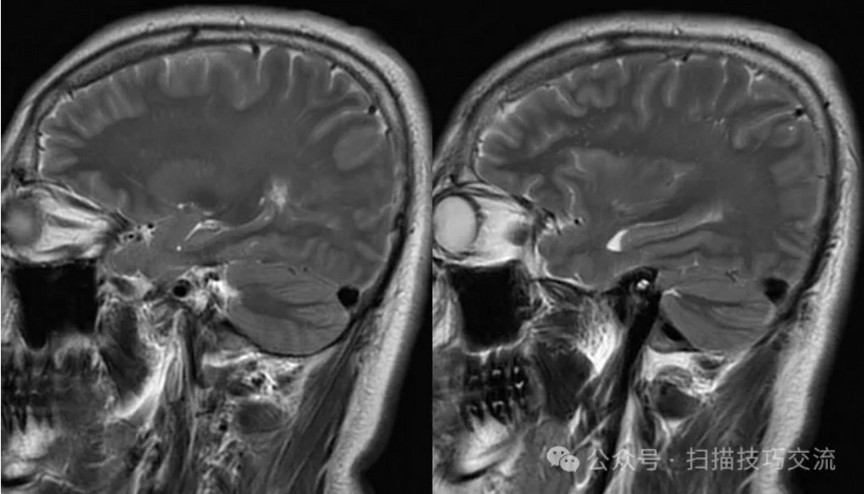

•汗腺分泌:正常,皮肤划痕正常反应。 •尿便障碍:无。性功能障碍无。 •专科情况:正常。不逐一罗列。 •辅助检查:01-05颅脑CT提示:1,上矢状窦、双侧横窦密度较高,请结合临床,必要时进一步检查;2,双侧脑室后角可疑稍高密度影,右顶叶局部脑沟密度可疑增高,建议进一步检查。 •初步诊断:静脉窦血栓

临床申请:颅脑平扫,静脉成像,磁敏感成像,颅内静脉血管黑血成像。

PC-MRV未见异常。

颅内静脉黑血成像,CUBE T1fs w/o +c,静脉窦未见异常。